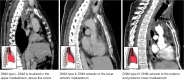

Case description: We analyze a retrospective case series of seven patients diagnosed with DNM between March 2019 and July 2022 at Hospital de la Santa Creu i Sant Pau. The primary oropharyngeal infection was peritonsillar abscess in three cases and odontogenic abscess in four. All patients showed symptoms of severe cervical infection and symptoms suggestive of mediastinitis. A cervicothoracic computed tomography (CT) scan confirmed the presence of cervical and mediastinal collections and emphysema in all cases. All patients were simultaneously evaluated by the otorhinolaryngology and thoracic surgery teams. Broad-spectrum antibiotic therapy was instituted pending culture. All the patients underwent urgent surgery, consisting of cervicotomy to control the cervical focus and unilateral or bilateral video-assisted thoracoscopic debridement and drain of the pleural cavities and mediastinum. Regarding the outcomes, no patients died, one patient (14.2%) underwent transcervical mediastino-thoracoscopy drainage only. In six patients (85.8%) we performed a combined transcervical and transthoracic approach. Reoperation was required in 3 (43%) cases. The parameter that indicated a poor clinical evolution in these patients was an increase in C-reactive protein and the infection extension on the cervicothoracic CT scan. The follow-up was 30 days from last surgery; there were no losses.